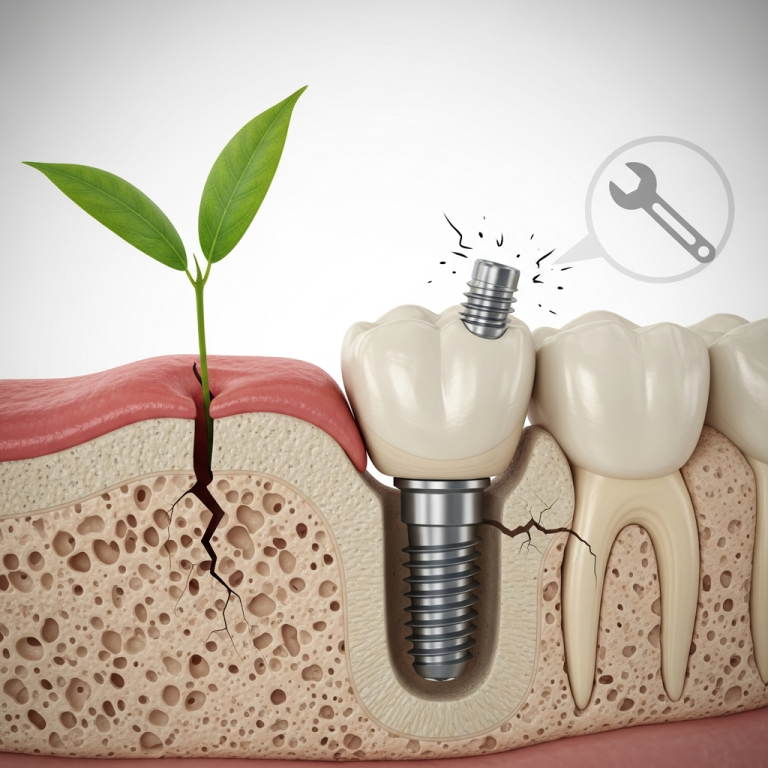

Rezistență Mecanică Superioară

- Rezistă la presiunile puternice din zona bazală.

- Risc extrem de scăzut de fractură sau fisurare.

- Durabilitate dovedită în situații cu volum osos redus.

Reducerea Riscului de Periimplantită

Suprafața netedă și netezibilă a zirconiului împiedică aderența bacteriană mai eficient decât titanul. Studiile indică o rată mai mică de complicații inflamatorii periimplantare.